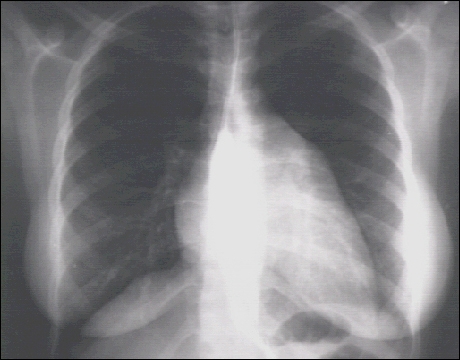

Chest X Ray

Labs - X Rays

PA and Lateral

Click on the xrays to enlarge them.

Choose the best interpretation of the chest X rays:

Left atrial enlargement and right ventricular enlargement

Left ventricular enlargement and pulmonary congestion

Calcified mitral annulus

Left ventricular enlargement and dilated aorta

Left ventricular enlargement and left atrial enlargement